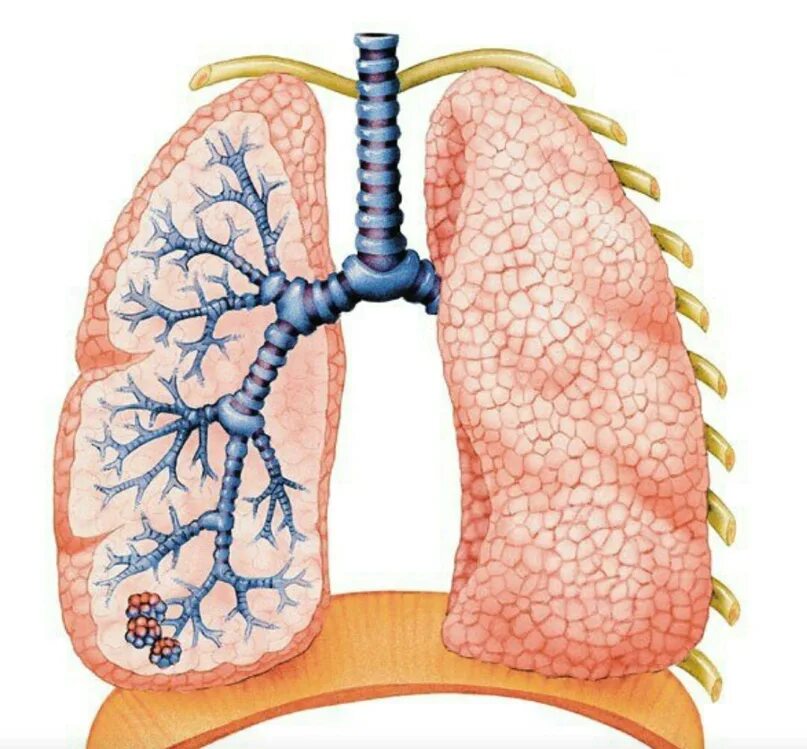

Дыхательная при пневмосклерозе